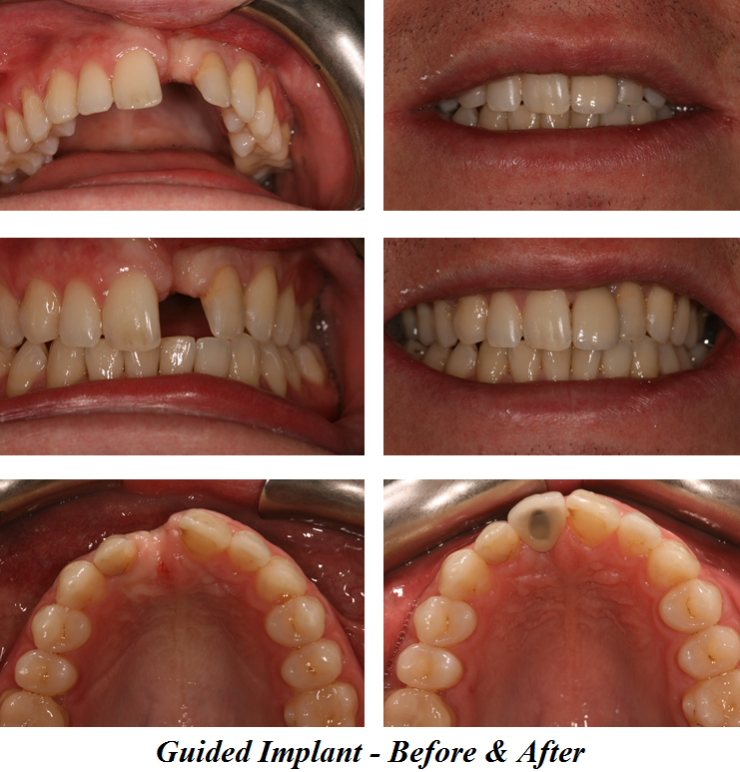

Guided Implant Surgery

Here at Aesthetic Dental Zone we embrace new concepts, guided implant surgery provides a solution where doctors can plan an implant virtually, and then accurately place an implant in the safest, predictable and efficient manner.

With guided surgery, we place the implant for the best aesthetic result and can predict accurately how much room will be needed for the crown and for any veneered superstructure that may go over the abutment.

From a single missing tooth to an edentulous jaw. It aids your Doctor to diagnose, plan the treatment and place your implants based on restorative needs and surgical requirements.

Following an initial Implant Consultation and CBCT scan (3D Scan of your jaw) we can get to work on your specific Implant case.Guided Implant Surgery takes away the need to be too invasive when placing your dental implants.

It is extremely accurate, more comfortable and the healing time is reduced.Guided Implant Surgery is a state of the art technology, trust in us to make your implant process as simple and easy as possible.